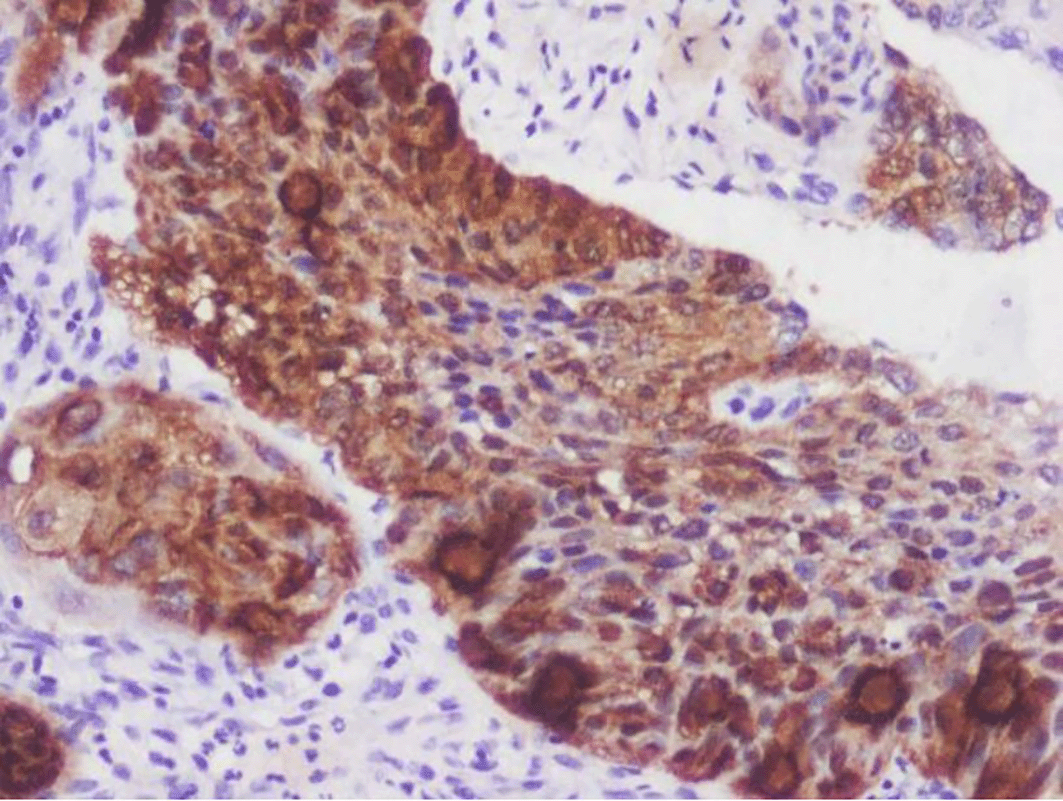

The IHC-stained slides were assessed separately by two pathologists. To avoid bias during assessment, they had no access to the patients’ clinical data. During the occurrence of inter-observer variation in assessment, specific slides were made to be viewed together, and their consensus opinion was taken into consideration ( Figures 1-4).

a18ea2fb-f248-4101-a9ac-0da1acc0b230_figure2.gif

Figure 2. Expression of E-CADHERIN.